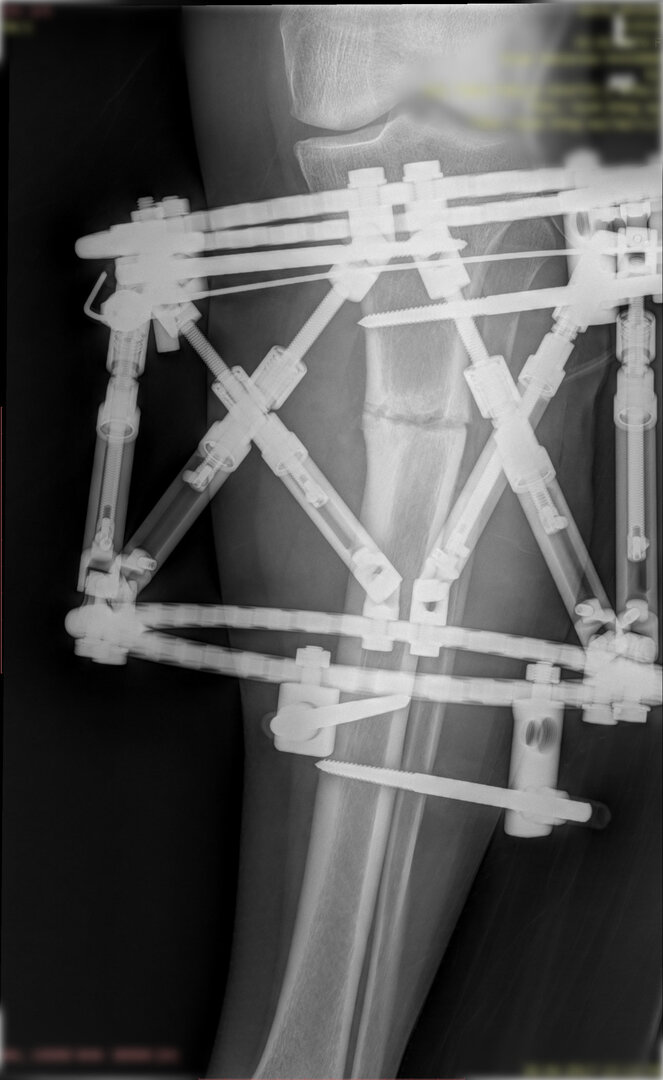

Deformitenin yeri ve miktarına bağlı olarak bilgisayar destekli sirküler eksternal fiksatör ile tedrici düzeltme yapılabilir. Bu sistemin avantajı düzeltme esnasında sistemle oynayarak yeni düzenlemeler yapmanıza izin vermesidir.

Bu ameliyat öncesi bir deformite analizi yapılıp hangi kemikte, normalden ne kadar sapma olduğu tespit edilir. Daha sonra bu kemiğe yine ostetomi yapılarak bu anormal sapma düzeltilir.  Bu düzeltme plak-vida veya intramedüller çivi ile akut olarak düzeltilebileceği gibi bilgisayar destekli sirküler eksternal fiksatör ile tedrici olarak ta yapılabilir. Hangi yöntemin hangi hasta için uygun olacağına hasta özelinde karar veriyoruz, ne tür cerrahi tedavi olması gerektiğini danışabilirsiniz.

Büyütmek için üzerine tıklayınız.